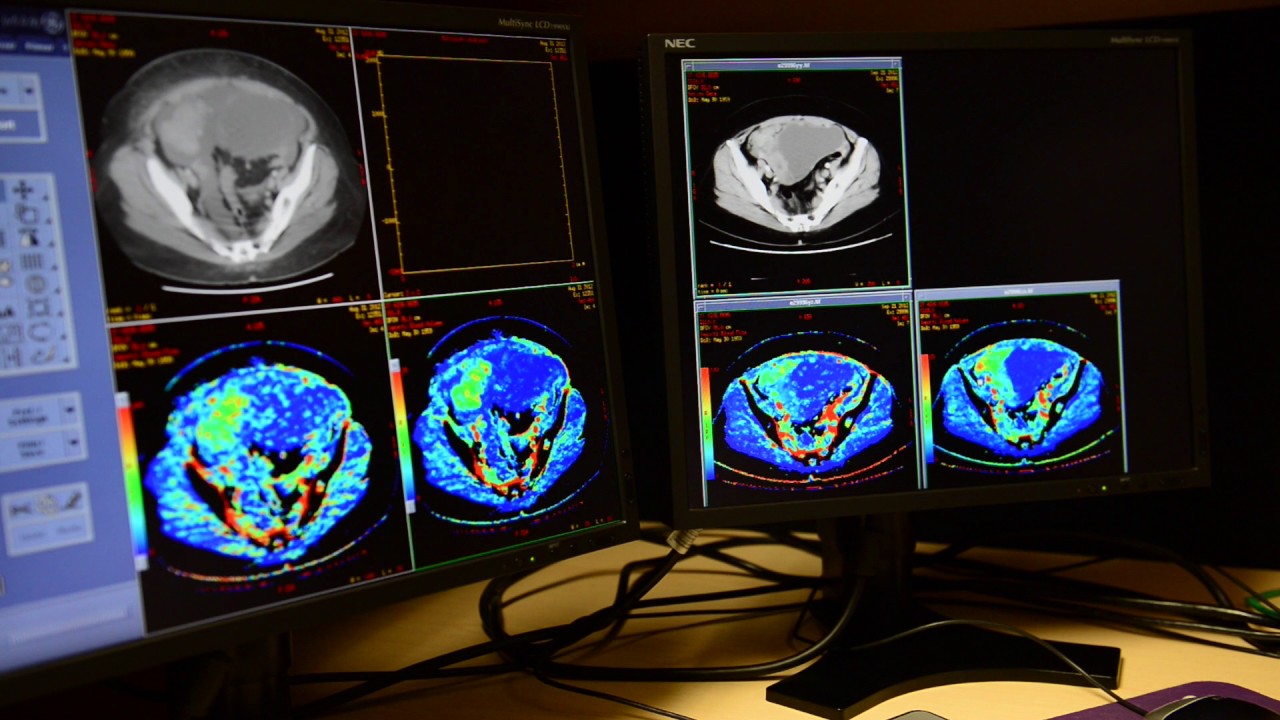

A technology designed at Lawson Health Research Institute and Western University can unlock new doors to answer whether or not patients are reacting to treatment for enhanced ovarian cancer. A multi-centre clinical experiment has confirmed that CT perfusion that measures blood volume and blood flow to tumors linked with ovarian cancer can offer a precise calculation of how well a therapy is working, permitting doctors the chance to better plan the therapy. Capital for the experiment was offered via the National Clinical Trials Network by the U.S. National Cancer Institute counting ECOG-ACRIN and NRG Oncology.

“CT perfusion is working on the change in flow of the blood to the tumor after and before the therapy,” said scientist at Lawson Health Research Institute, Ting-Yim Lee. Lee is also a medical physicist at St. Joseph’s Health Care London and a professor at Schulich School of Medicine & Dentistry of Western University. “In this specific case, we can witness that the flow of blood seems to reduce in those who will live longer without signs, whereas for those whose signs will persist within 6 months, we witnessed the flow of blood towards the tumor elevated after their therapy.”

Designed by Lee and his squad at Robarts Research Institute of Western University, CT perfusion employs X-ray dye in amalgamation with current CT scanners to calculate flow of the blood. The tech is already adopted all over the world to evaluate flow of the blood to the brain post the stroke. This clinical experiment for use in ovarian cancer occurred across 19 U.S. centers, and also confirmed that the tech is implemented with no trouble onto any current CT scanner, and needed least training to be victorious.